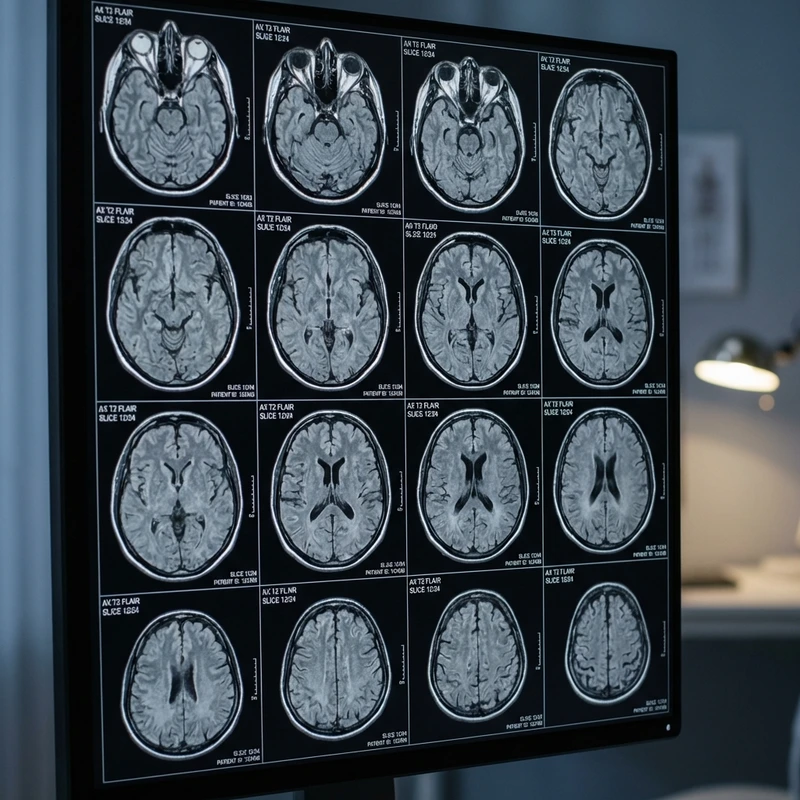

The GE SIGNA Artist EVO 1.5T is designed to offer the ultimate examination experience. It features a wide 70cm bore for greater comfort and uses revolutionary AIR Coils, which are lightweight and flexible like a blanket, embracing the patient's body.

Incorporates AIR Recon DL technology, a deep learning system that reconstructs the image by removing noise and improving clarity in real-time.

Brain, Spine with exceptional detail.